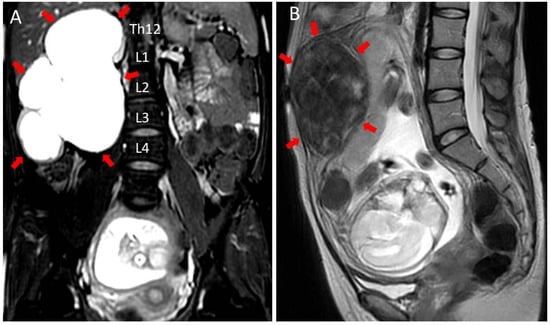

2. Case Presentation

| Present case (2022) | 31 | 0 | None | Right | Flank pain | TAU/MRI | 26th | 0.65 | None | Aspiration (3 times) | Vaginal delivery/36th |